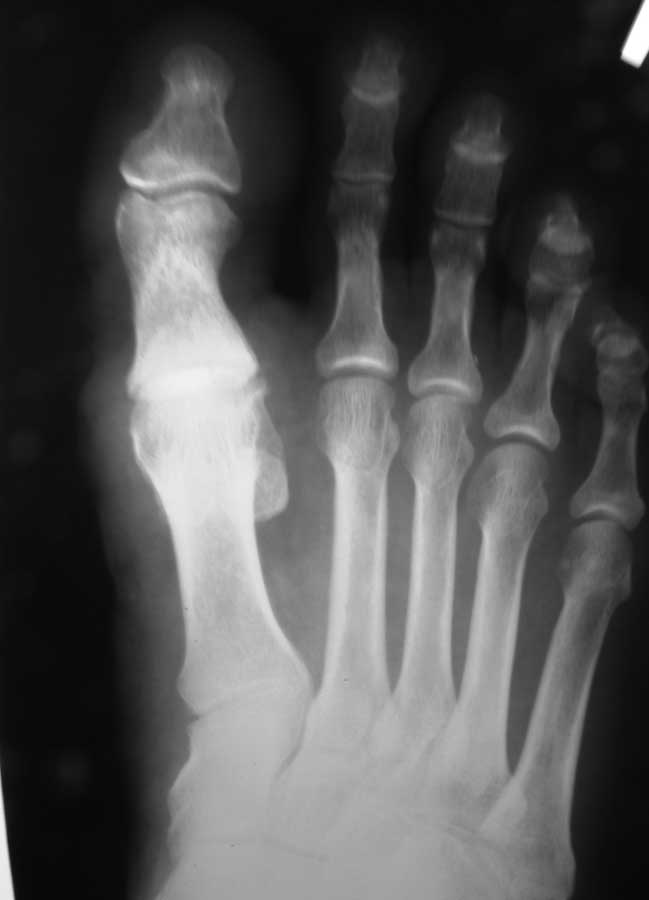

Здравствуйте, коллеги. Помогите с тактикой дальнейшего лечения.Мужчина 52 года, активный физически. В марте 2012 оперирован по поводу ДОА плюсне-фалангового сустава 1 пальца, сделана резекция основания основной фаланги и остеофитов головки плюсневой кости. Послеоперационное лечение: массаж, физиотерапия. В настоящее время беспокоят сильные боли в суставе, сохраняется ограничение движений. Дальнейшая тактика: артродез ПФС?, Эндопротезирование ПФС?, повторная резекция основной фаланги? Мнения наших коллег разделились. На фотографиях: вид стопы в настоящее время, рентгенограммы до операции, после операции, в настоящее время. Прошу прощения за неважное качество снимков.

Любой из рассматриваемых Вами вариантов имеет право на жизнь. Наиболее вероятная причина болей - слишком экономная резекция фаланги: адекватная декомпрессия сустава не достигнута. Протезирование 1 ПФС у молодого активного физически мужчины предполагает ревизию уже через несколько лет. Так что артродез или повторная резекция основной фаланги - равнозначные оптимальные варианты.

Причинами неудовлетворительного результата могли стать следующие: 1) недостаточная величина резекции основной фаланги и 2) "стирание" оставшегося хряща головки 1 ПК опилом фаланги. В своей практике обычно убираем больше кости (примерно 1/4 - 1/3 длины фаланги), опил моделируем, укрываем лоскутом капсулы или Артелоном (специальный биодеградируемый скользящий материал).

1) ничего не делать (только консервативное лечение) и посмотреть в динамике. Не исключено, что болевой синдром уменьшится (ориентировочно, через 6 мес. после операции), объём движений незначительно увеличится, и больной к Вам больше обращаться не будет.

2) повторная резекция основания фаланги (опил необходимо укрыть), круговой релиз 1 ПФС. Ранняя разработка движений в суставе.

3) эндопротезирование 1 ПФС, если это посильно для больного. На операции наверняка столкнётесь с тугоподвижностью, тщательно мобилизуйте сесамовидные кости и сухожилия коротких сгибателя, разгибателя, отводящей мышцы.

4) артродез 1 ПФС. Наименее привлекательный вариант в плане функции. Пациент вернётся к тому, с чего начал (Hallux rigidus), только уже в необратимом варианте.

Наилучшим вариантом представляется вар. 2, так как сохраняется собственная головка 1 ПК, которая хорошо переносит нагрузки (а в фазу заднего толчка на неё приходится до 70% веса человека). Имеем достаточно много отдалённых результатов: амплитуда движений в 1 ПФС 30 - 45 градусов, болевой синдром не беспокоит.

Ничего не могу сказать про отдалённые результаты эндопротезирования (8 - 10 лет и больше), ближайшие - хорошие. В конце концов, при возникновении проблем в любом варианте никогда не поздно сделать артродез.